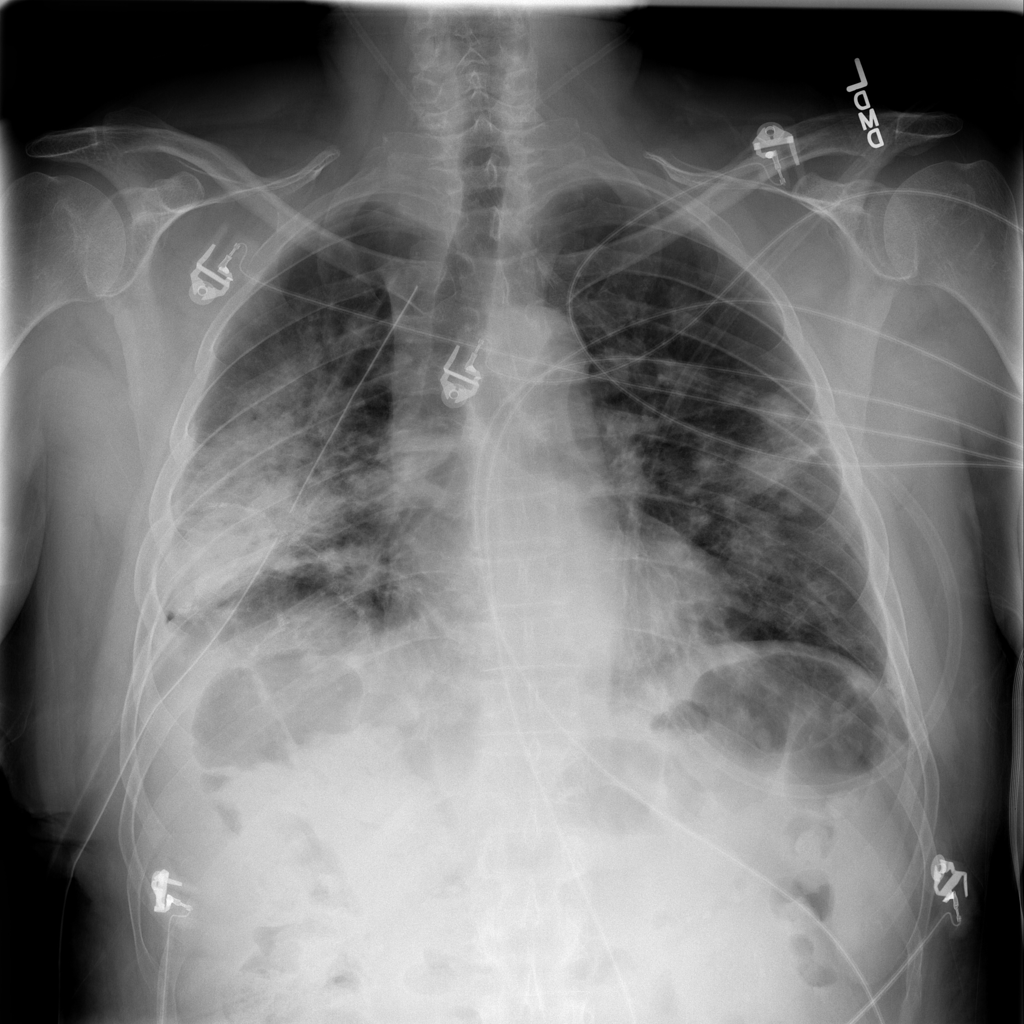

PAT-531A · IMG-006Consolidation

PAT-531A · IMG-006

PA